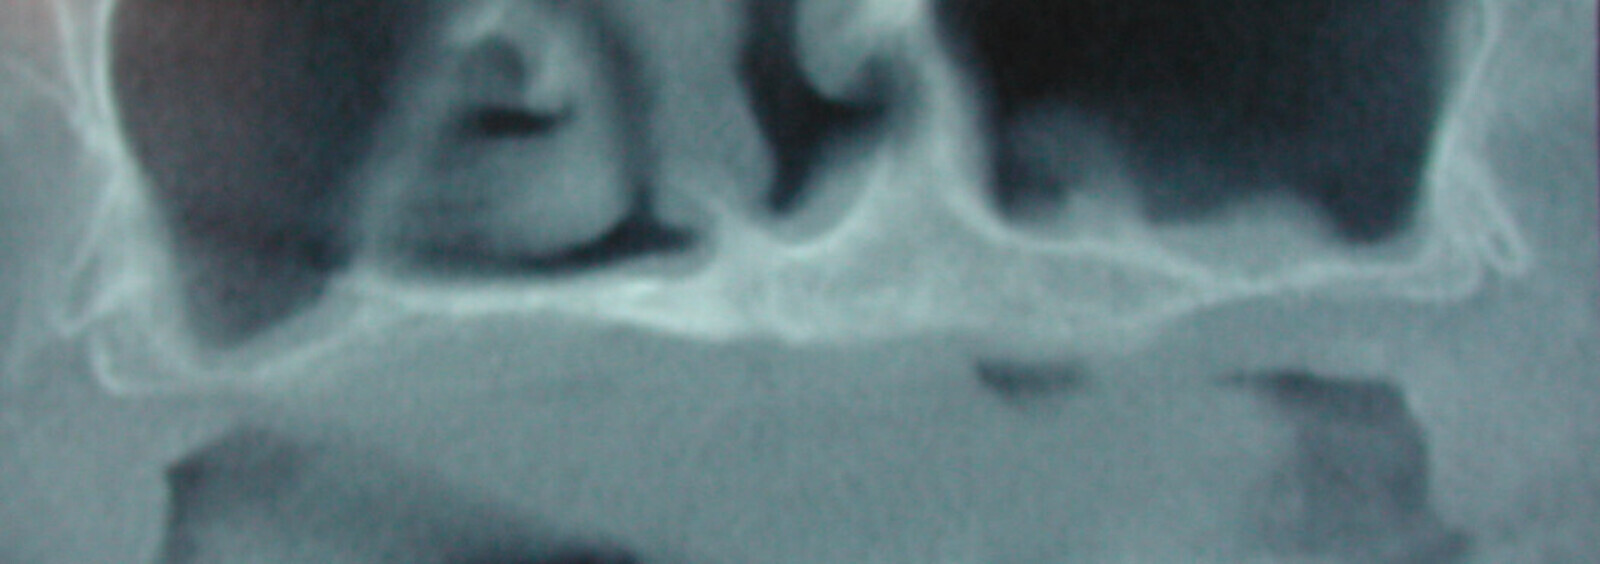

Fig. 7 : Mise en évidence d’un « soulevé » de membrane sinusienne à l’aide d’un implant Fractal (Visy, France) 45 jours après une ostéoactivation.

On va piquer en passant délicatement de la muqueuse buccale à travers la corticale pour finir par piquer un peu la muqueuse sinusale. Cette technique non invasive va créer un petit saignement sous la muqueuse sinusale et un caillot va s’organiser sous cette muqueuse, et finalement s’ossifier à l’abri des micromouvements, à l’abri des bactéries suite à l’absence de fenestration, et donner finalement une corticale renforcée et une élévation du fond sinusal pouvant atteindre 5 à 8 mm. De plus, on est certain dans ce cas de récupérer de l’os vivant puisque le patient l’a reconstruit lui même suite à cette stimulation.

On va pouvoir y poser des cylindres en prenant soin de ne pas forer jusqu’au bout de la hauteur osseuse obtenue en sous sinusal.

De cette manière, en posant l’implant délicatement, on va provoquer encore une petite élévation du fond osseux poussé par l’apex de l’implant. Toutefois, ces cylindres seront actuellement laissés en nourrice 6 à 9 mois avant d’être mis en charge.